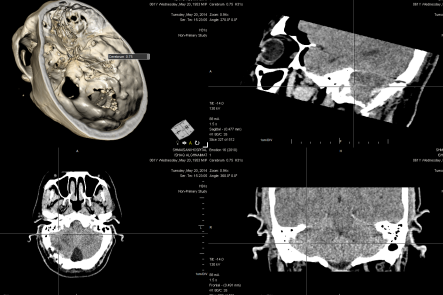

20-MAY-2014  ISHAQ MUHAMED GHNEMAT  60 YEARS  EARLY RECURRENCE OF RIGHT TRIGEMINAL NEURALGIA.

CT-scan was done before surgery to see the craniotomy site and the the presence of possible hematoma or huge infarctions. There was an infarction of the right cerebellar pole, without any shift to major structures.

The CT-scan done before surgery showing the infarction and the Teflon patch is missing.